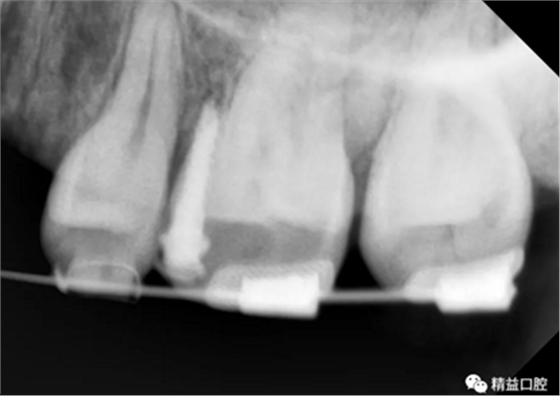

內(nèi)收過程中,李醫(yī)生在上頜左右各植入一顆支抗釘,以達到更好的內(nèi)收效果。

因下頜唇傾比較嚴重,加上門牙牙根在矯正前已經(jīng)有大量吸收前提下,為了實現(xiàn)更好的矯正效果,李醫(yī)生選擇了拔除下頜左一,內(nèi)收下牙,給上牙內(nèi)收提供更多的空間。